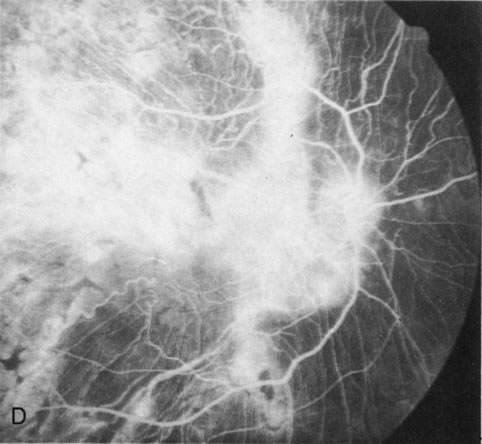

Fig. 1. Retinitis pigmentosa. A. A typical area of bone spicule pigmentation. B. Diffuse dye leakage is apparent throughout the posterior pole. C. The early angiogram shows dilated and irregular retinal radial peripapillary capillaries and perifoveal retinal capillaries. D. Leakage from these vessels are evident in the late angiogram.

Of more clinical importance is the role of FA in the diagnosis and treatment of cystoid macular edema (CME) (Fig. 1C and D). Stereoscopic FA indicates that the leakage, which may be diffuse or have the typical petaloid stellate appearance of CME, can come from the perifoveal retinal capillaries, from the choroid through the RPE, or from a combination of both sources.4 With the recent suggestion that CME in RP may be successfully treated with acetazolamide,5, 6 FA is thus important to document the diagnosis of CME, establish the origin(s) of leakage, and follow patients during and after therapy.